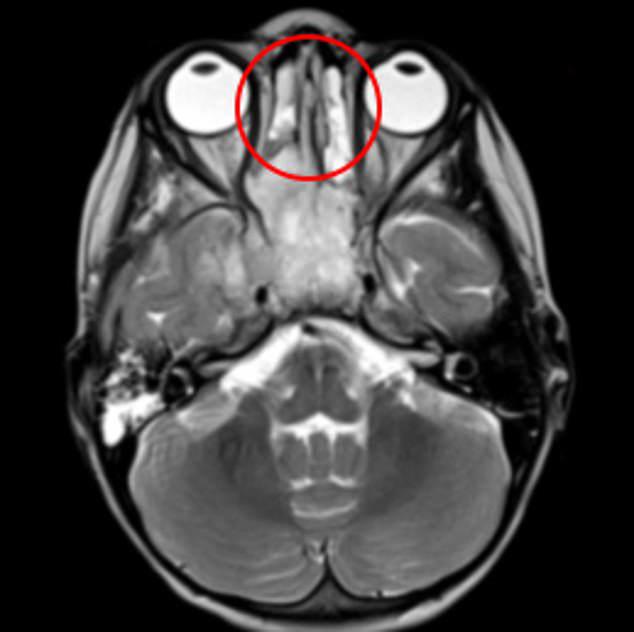

Ba tuần sau khi gặp các triệu chứng khó hiểu, cô bé cuối cùng được đưa đi quét não khi gặp phải các vấn đề như đau trong khi ăn, lỗ mũi bên phải khó thở. Kết quả cuối cùng cho thấy cô bé có một khối u lớn trong khoang mũi. Bé bị chẩn đoán mắc bệnh ung thư khoang mũi hiếm gặp. Căn bệnh tấn công xương và một phần mô bên trong khoang mũi, thậm chí đã lan một ít đến vùng xương sọ, cơ hàm và cả một số tế bào não bộ.